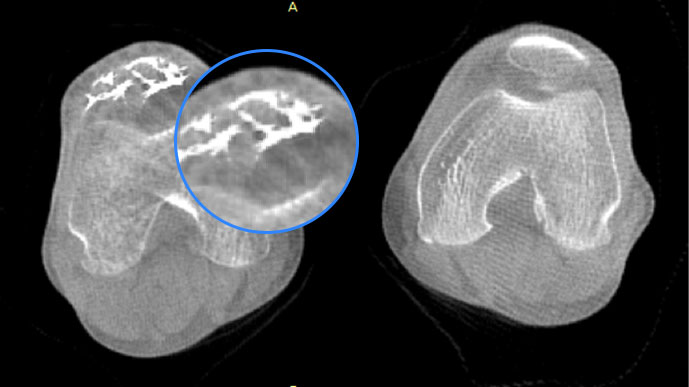

FOV 250mm

FOV 350mm